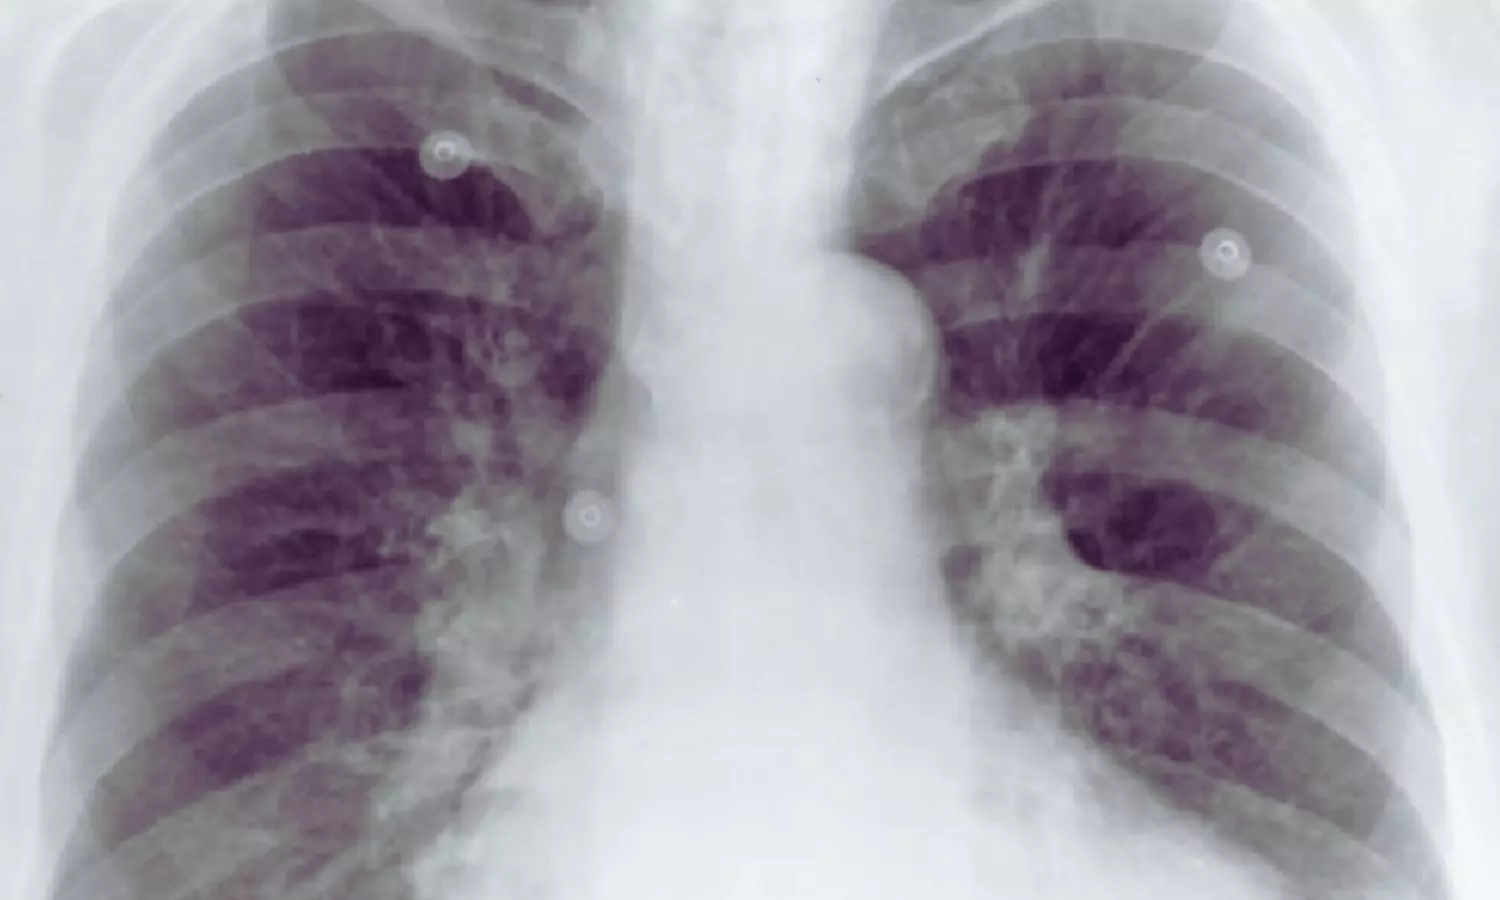

Finland: Aortic calcifications (ACs) visible on routine chest radiographs may signal worse survival prospects for patients undergoing minor lower limb amputation, a study published in JVS: Vascular Insights has shown.The research, led by Miska Vuorlaakso from the Faculty of Medicine and Health Technology at Tampere University, Finland, suggests that this simple imaging finding could serve as an important prognostic marker in a high-risk vascular population.The investigators conducted a single-center, retrospective observational study involving 383 patients who underwent minor amputations below the ankle between 2007 and 2020. All participants had received an upright anteroposterior chest x-ray within three months before surgery. The amputations were performed primarily due to complications of peripheral arterial disease and diabetes—conditions strongly linked to systemic atherosclerosis.Two researchers independently reviewed the preoperative chest radiographs to determine the presence and extent of aortic calcifications. Calcifications were graded using three classification systems—the Symeonidis system, the Tian system, and a newly introduced AV classification—categorizing findings as none or mild, moderate, or severe based on the size and distribution of calcified deposits. Severe calcification was defined as circumferential or near-circumferential involvement of the aorta. The study led to the following findings:A total of 62.1% of patients had detectable aortic calcifications on preoperative chest x-ray.Severe AC was present in 21.9% of patients.In unadjusted analyses, severe AC was associated with more than a threefold increased risk of poorer overall survival (HR 3.165).Severe AC was linked to nearly threefold higher risk of reduced amputation-free survival (HR 2.972).Severe AC was also associated with a significantly increased risk of impaired leg salvage (HR 2.495).After adjustment for other variables, severe AC remained significantly associated with worse overall survival and amputation-free survival.The association between severe AC and leg salvage did not remain significant in multivariable analysis.The overall presence of ACs was associated with poorer overall survival (HR 1.669).The presence of ACs was also linked to reduced amputation-free survival (HR 1.587).Lower extremity amputation represents a serious and increasingly frequent complication of advanced peripheral arterial disease and diabetes, often accompanied by diminished quality of life and elevated mortality risk. The high prevalence of aortic calcifications observed in this cohort reflects widespread systemic atherosclerosis, which may contribute to adverse outcomes after surgery.The authors emphasize that chest radiography is inexpensive, widely available, and routinely performed before surgery. Recognizing aortic calcifications on these images could therefore enhance preoperative risk assessment without requiring additional testing. Incorporating this readily identifiable marker into clinical decision-making may help clinicians better stratify risk and tailor treatment strategies for patients facing limb-threatening conditions.Reference:Vuorlaakso, M., Kaartinen, I., Hirvonen, J., & Arponen, O. (2026). Aortic calcifications on chest radiographs associated with survival after lower extremity minor amputation. JVS-Vascular Insights, 100373. https://doi.org/10.1016/j.jvsvi.2026.100373